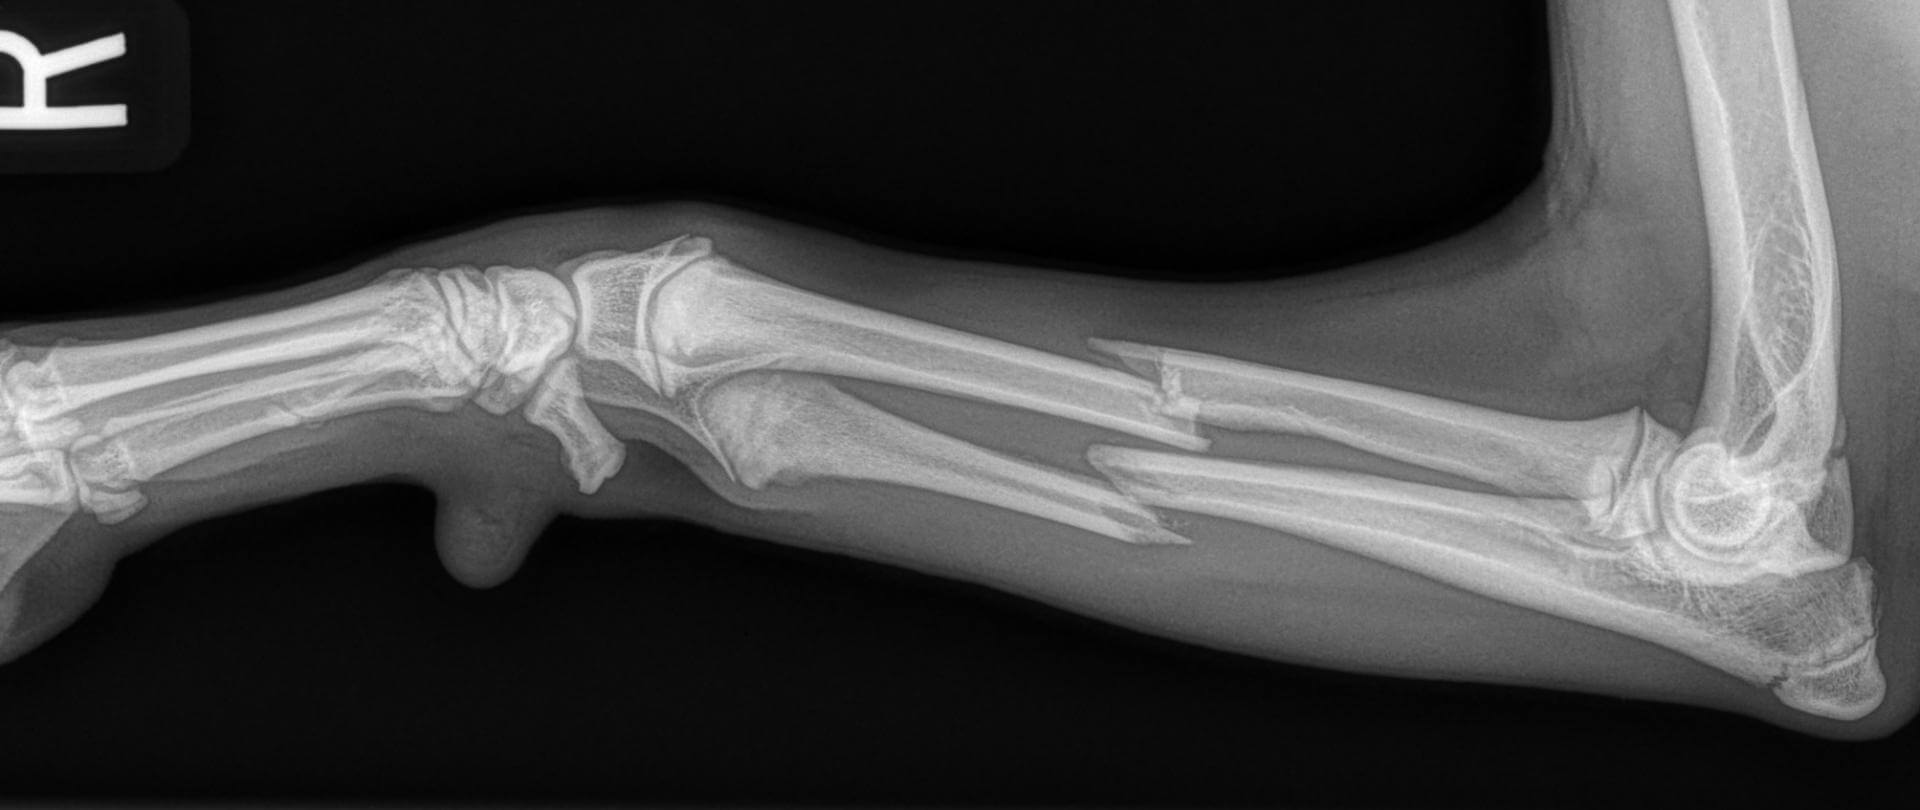

Dog leg fracture xray. Canine radius and ulna limb fracture radiograph

Dog X Ray Showing Radius and Ulna Fracture. Cranial View Stock Image Radius Ulna Fracture Dog Splint this video show how to apply a splint that will be functional and comfortable (therefore well tolerated by the dog and the owner!). as mentioned earlier, distal radius/ulna fractures, especially those in small and toy breed dogs, addressed with external coaptation alone commonly result in malalignment or nonunion. — 1) any toy breed dog with a radius. Radius Ulna Fracture Dog Splint.